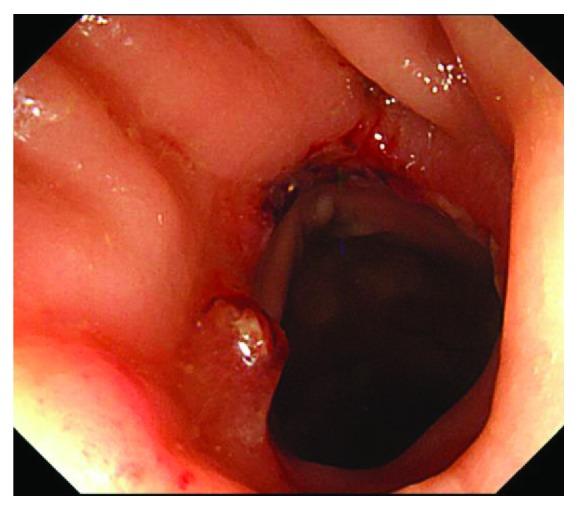

The double stapling technique has greatly facilitated intestinal reconstruction, particularly for anastomosis after anterior resection. However, anastomotic stenosis may occur, which sometimes requires surgical treatment. Redo surgery with reresection and reanastomosis presents a high risk of complications. Treatment methods need to be selected depending on the degree and location of stenosis. In an effort to propose a new resolution, reporting new cases and sharing valid experiences are necessary. An 82-year-old man diagnosed with rectal cancer had undergone laparoscopic anterior resection. Endoscopic balloon dilation performed for anastomotic stenosis had failed. Therefore, colostomy with double orifice was constructed on the oral side at 10 cm from the stenosis. Approaching from the anal and stoma side, the anastomotic stenosis was resected using a circular stapler. The colostomy was closed 1 month after surgery. Stenosis resection using a circular stapler requires the following steps: (1) passing the center shaft through the stenosis, (2) inserting the anvil head into the oral side of the stenosis, and (3) attaching the anvil head to the center shaft. This method can resect the stenosis using a circular stapler without being affected by postoperative adhesion in the pelvis. Compared to endoscopic balloon dilation, resection of the stricture by the circular stapler is thought to be reliable. This technique is particularly effective for localized stenosis, including anastomotic stenosis. It is considered that this method is minimally invasive and is low risk for complications. This method can contribute to the useful surgical option for refractory anastomotic stenosis after anterior resection.

双吻合器技术极大地促进了肠道重建,尤其是在前切除术后的吻合方面。然而,吻合口狭窄可能会发生,有时需要手术治疗。再次切除和重新吻合的再次手术并发症风险很高。治疗方法需要根据狭窄的程度和部位来选择。为了提出一种新的解决方案,报告新病例并分享有效经验是必要的。一名82岁被诊断为直肠癌的男性接受了腹腔镜前切除术。因吻合口狭窄进行的内镜球囊扩张失败。因此,在距狭窄处10 cm的口侧构建了双口结肠造口术。从肛门侧和造口侧进入,使用圆形吻合器切除吻合口狭窄。术后1个月关闭结肠造口。使用圆形吻合器切除狭窄需要以下步骤:(1)将中心轴穿过狭窄处,(2)将钉砧头插入狭窄处的口侧,(3)将钉砧头连接到中心轴上。这种方法可以使用圆形吻合器切除狭窄,而不受盆腔术后粘连的影响。与内镜球囊扩张相比,用圆形吻合器切除狭窄被认为更可靠。该技术对包括吻合口狭窄在内的局限性狭窄特别有效。认为这种方法微创且并发症风险低。这种方法可为前切除术后难治性吻合口狭窄提供有用的手术选择。